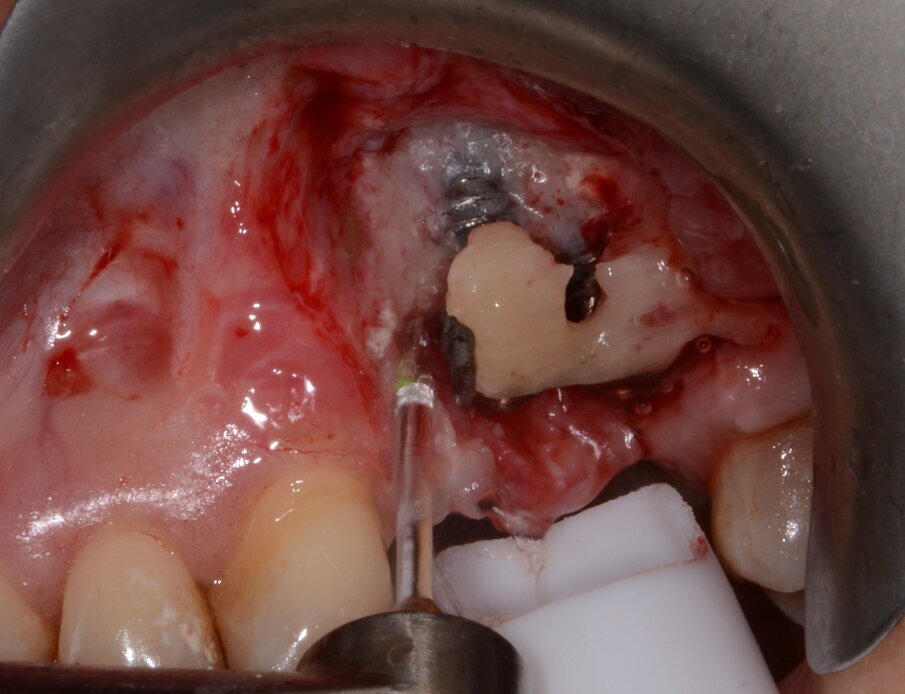

In Case 2, the patient preferred a surgical procedure with bone augmentation, as a consequence of bone graft complication and graft exposure (Figs. 8–12).

Fig. 9: Granulation tissue visible after flap elevation.

Fig. 10: Granulation tissue removal with Er:YAG laser.